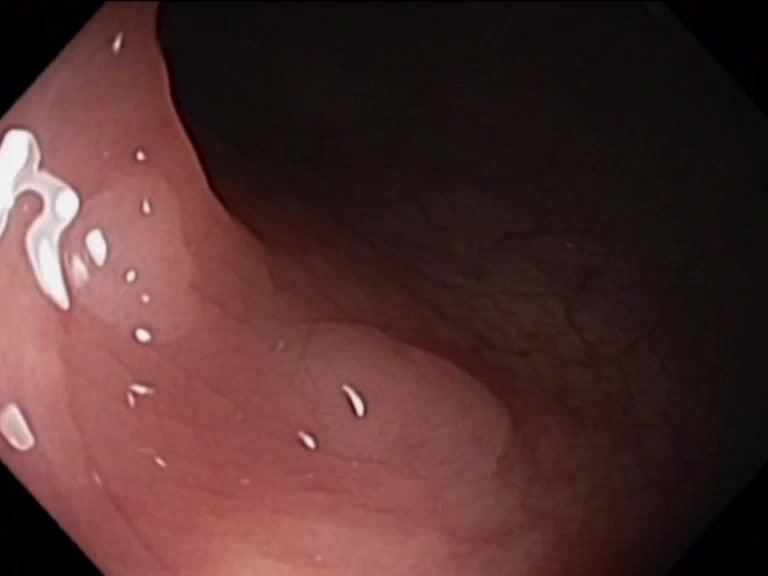

| Lesion | White Light Frame | NBI Frame | White Light Video | NBI Video | Camera Calibration |

| hyperplasic_01 |  |

|

WL.mp4 | NBI.mp4 | cam.xml |